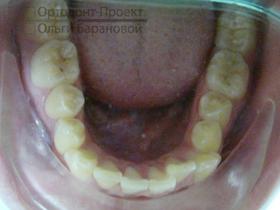

Брекеты Damon установлены:

На текущем этапе ортодонтического лечения использование брекетов сфокусировано на расширении зубного ряда в области второго и четвертого зубов, при этом на системе установлены специальные пружины.

Через пять месяцев начинается новый этап — возвращение клыков на их естественное место в зубном ряду. Вторая дуга обеспечивает стабильное положение передних резцов.